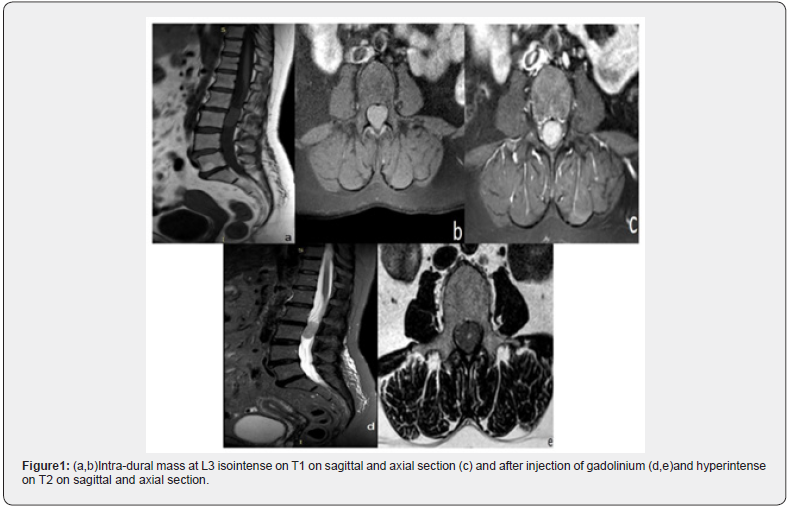

A 58-year-old female patient was admitted with complaints of low back pain and bilateral sciatica. Her symptoms started 6 months before her admission and have worsened over time. The patient took a symptomatic treatment without any amelioration. On examination, her general condition as well as her cardiorespiratory system was normal. The neurologic examination did not reveal any specific signs except a classical lumbar spinal syndrome. Nevertheless, it is important to mention that there was no neurologic deficit. A provisional clinical diagnosis of lumber disc herniation was made and a Magnetic Resonance Imaging (MRI) was suggested. The MRI showed an intra-dural lesion at L3 measuring 31 mm of height. The mass was well demarcated and had an isointense signal on both T1-and T2-weighted images with intense and homogeneous gadolinium enhancement (Figure1). There was no foraminal extension and no associated bone destruction.